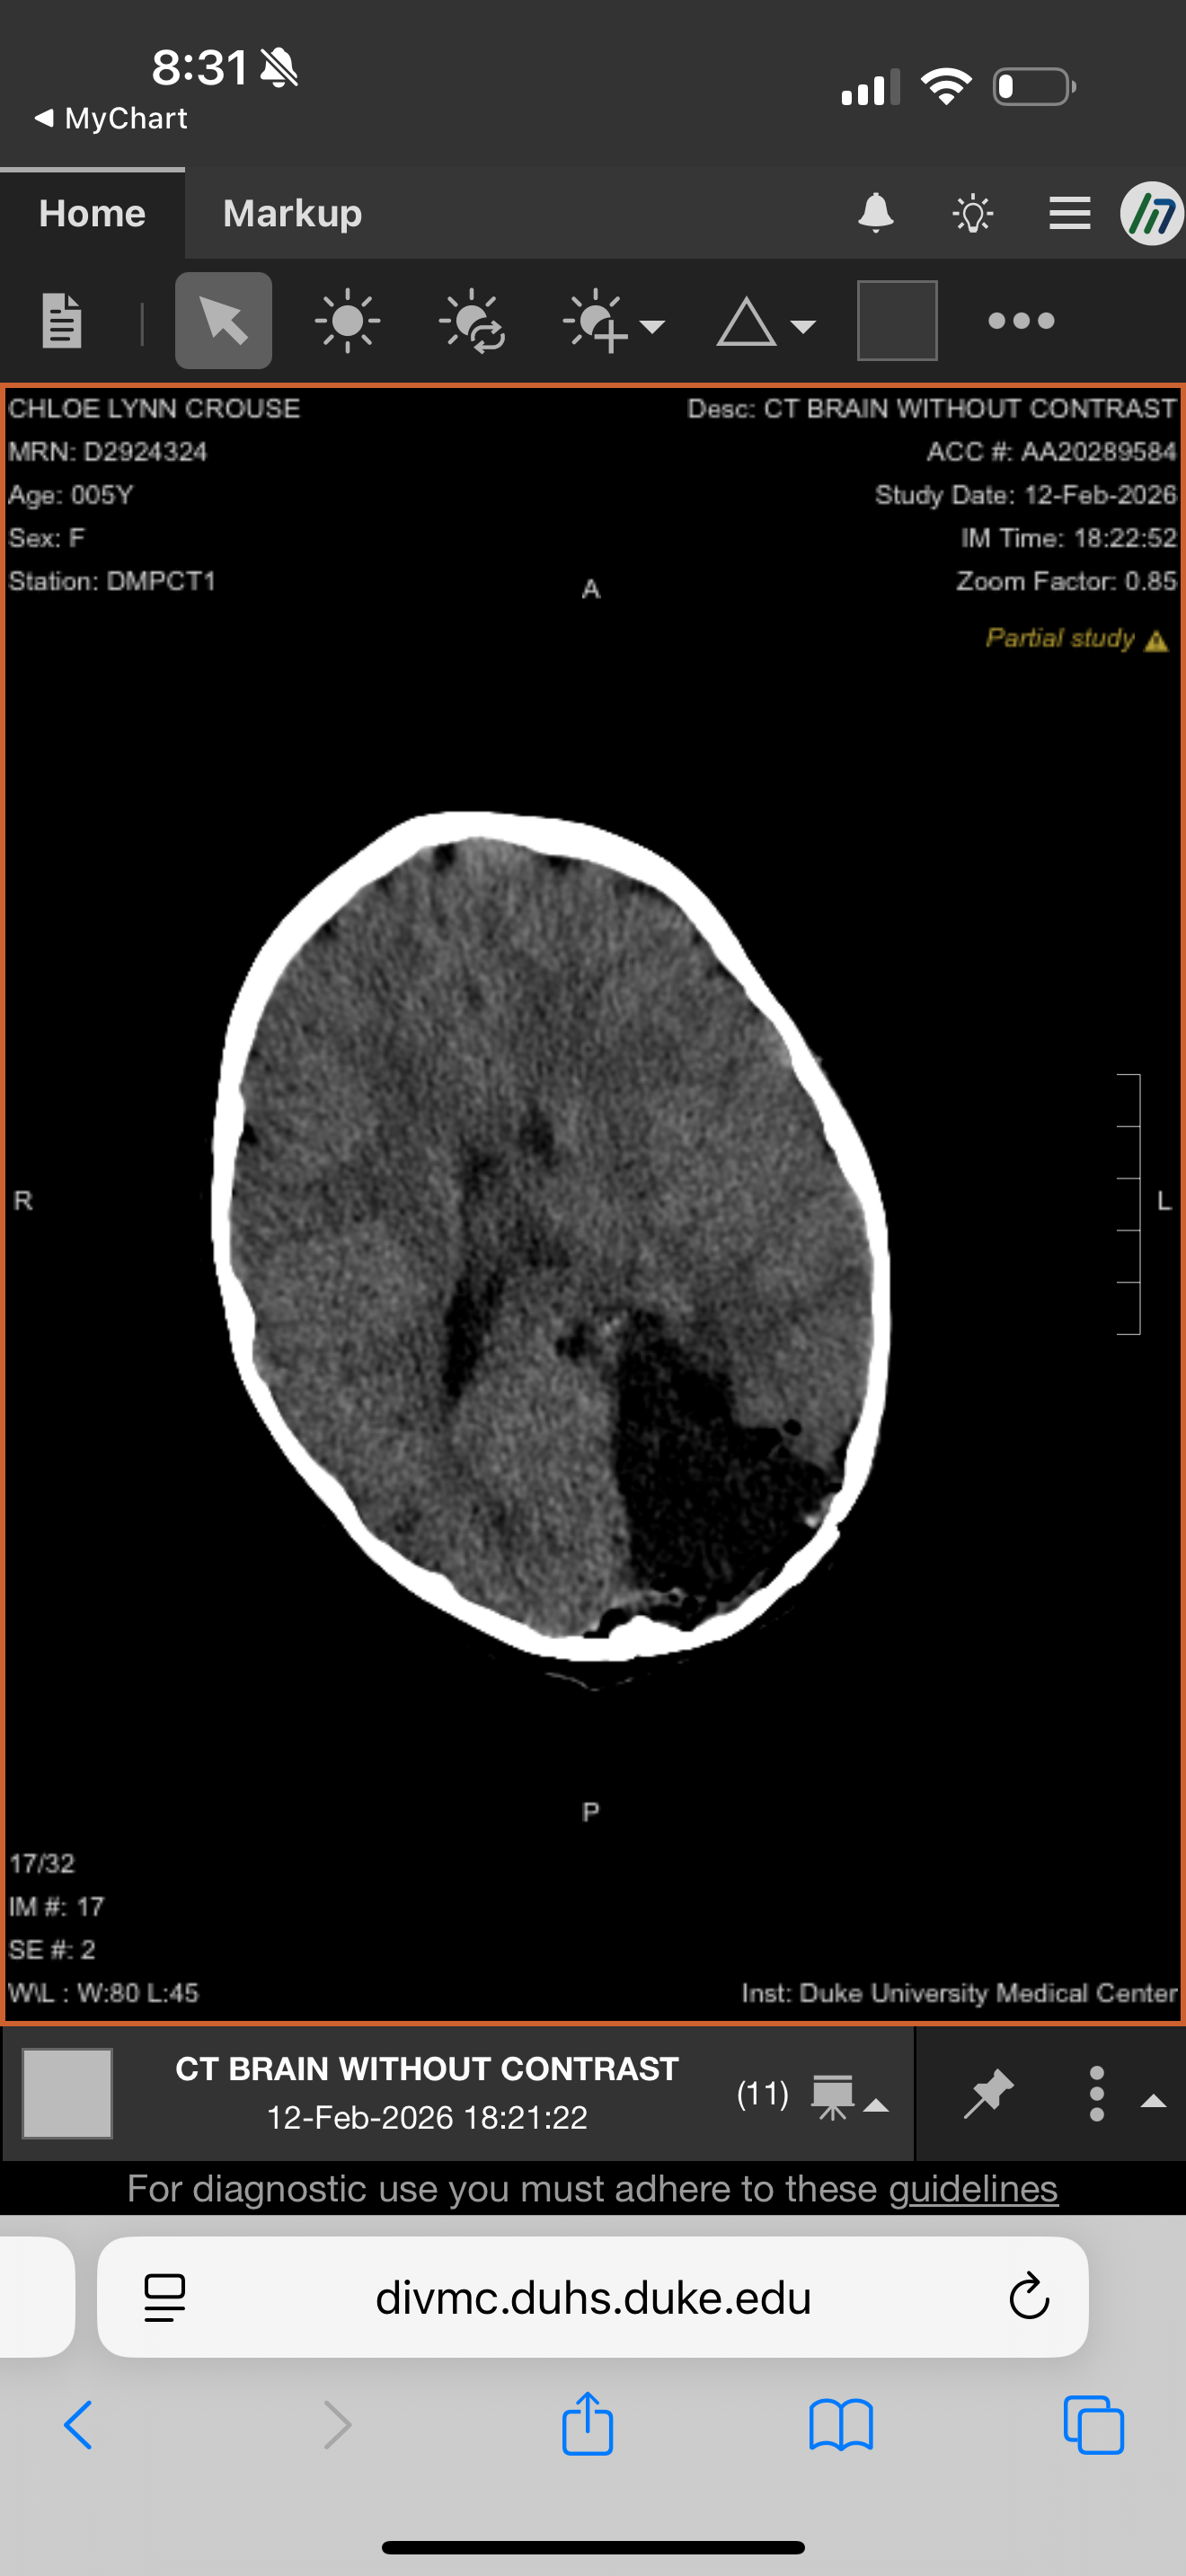

Chloe, my daughter, was diagnosed with a low grade tumor in the occipital lobe of her brain in October 2024. Since then, our family has faced a whirlwind of medical challenges. Chloe has bravely endured a brain biopsy, countless EEGs, MRIs every few months, an SEEG procedure, frequent blood draws, and an at-home oral chemotherapy regimen. She’s also been on three different seizure medications. Just this month, Chloe underwent surgery to finally remove the tumor. Throughout this journey, she experienced 3-4 focal seizures every day that we could see, and many more that were invisible to us. The toll on her daily life has been immense—she’s missed a tremendous amount of school for appointments and procedures, and the recovery process is ongoing. After surgery, Chloe will be out of school for at least six weeks. She now needs physical and occupational therapy because the tumor removal has caused her to lose her peripheral vision on the right side. To help her catch up with her peers, she’ll also need tutoring due to the significant time missed in class. The financial strain has been overwhelming. Funds raised will go directly toward Chloe’s therapy, tutoring, travel for medical care, and home expenses that have piled up from missed work. We are deeply grateful for all the support and prayers we’ve received so far. Thank you to everyone who has contributed or is able to help in Chloe’s recovery. This journey has been a struggle both mentally and financially, and your kindness means the world to us.